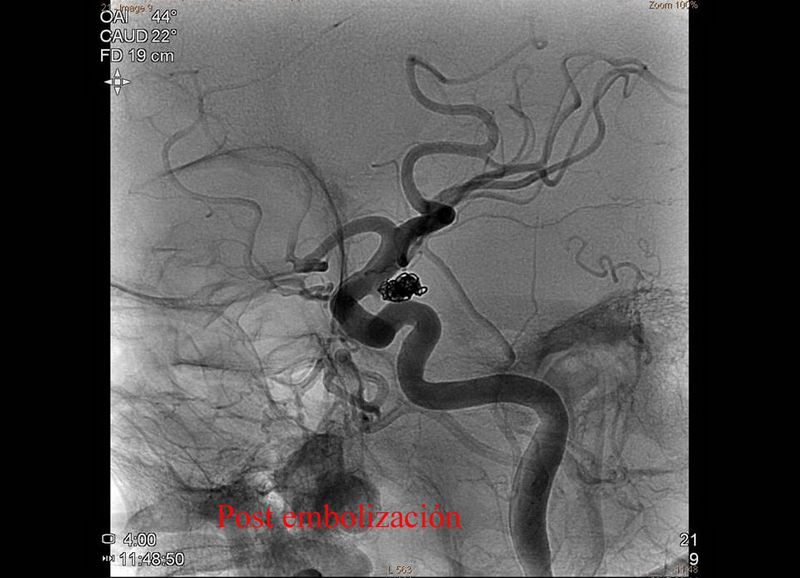

Aneurisma repermeabilizado de A comun post